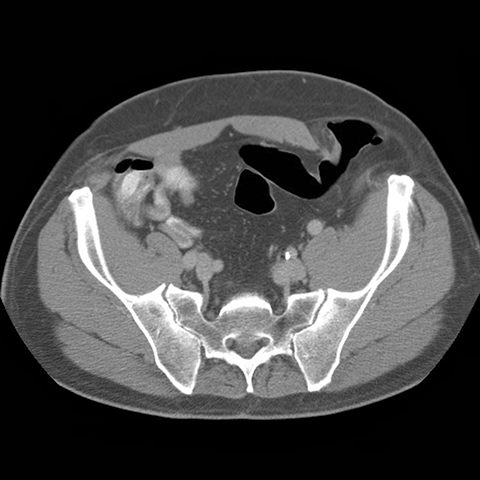

59 year-old male presents with an abdominal mass and pain. [3 of 5]